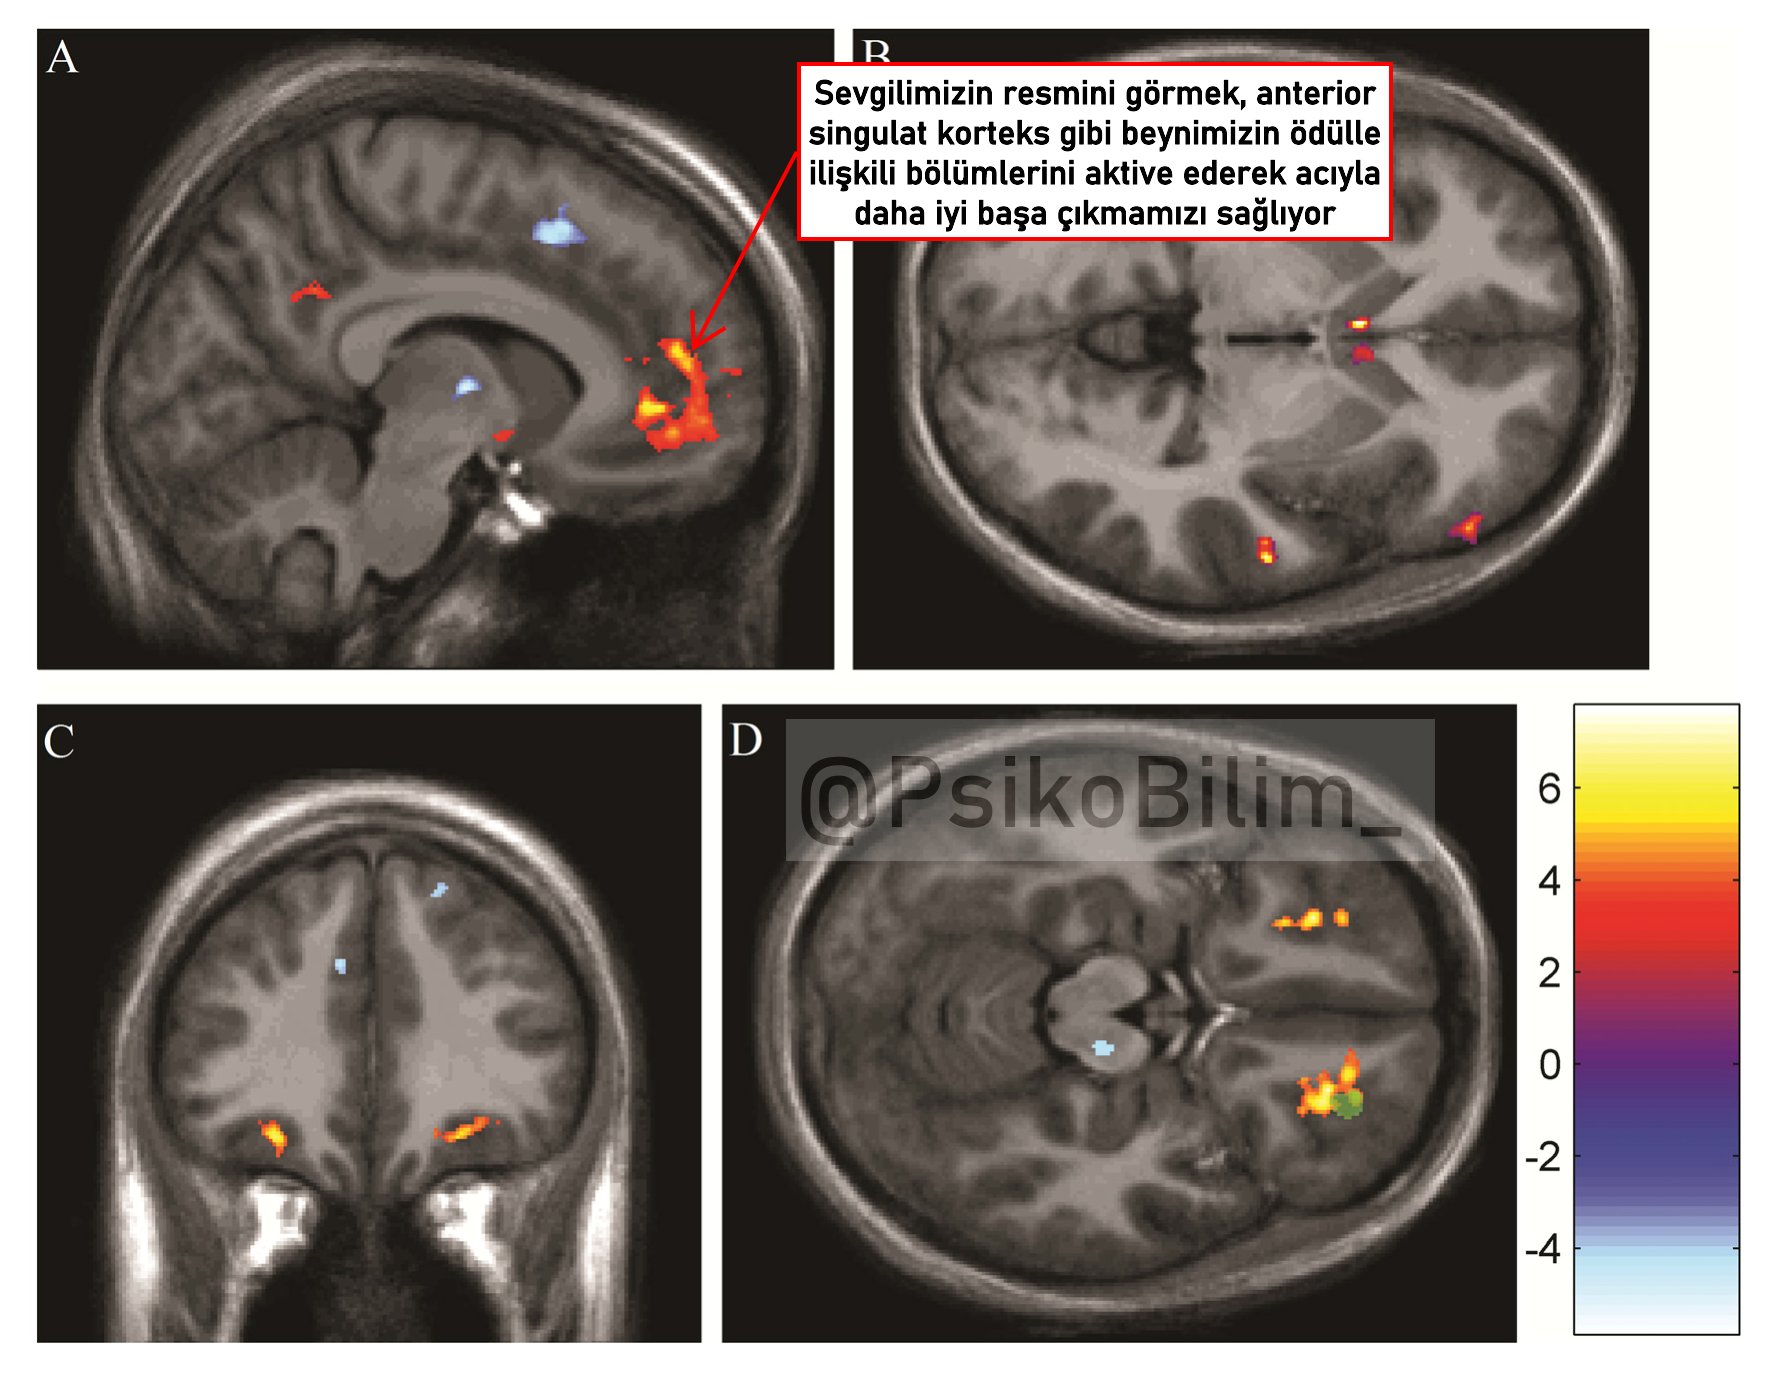

Yeni bir araştırmaya göre, sevgilimizin resmini görmek, beynimizdeki ödül merkezlerini aktive ederek ağrıyı azaltabiliyor. Stanford Üniversitesi tarafından yapılan bir çalışmada, romantik partnerlerin fotoğraflarını gören katılımcıların, deneysel olarak oluşturulan ağrı düzeylerinde azalma yaşadığı tespit edildi. Araştırmada, yoğun aşkın, beynin ödül merkezlerini aktive ederek, güçlü ağrı kesiciler veya yasadışı uyuşturucular kadar etkili olabileceği ortaya kondu. Stanford Üniversitesi'nde yapılan bu çalışmada, katılımcılar beyin taramaları sırasında termal ağrıya maruz bırakıldılar ve bu süreçte sevgililerinin fotoğraflarına baktılar. Sonuçlar, bu katılımcıların ağrı düzeylerinin belirgin şekilde azaldığını gösterdi​ (ScienceDaily)​​ (Stanford Medicine)​. Bu bulgular, aşkın beyindeki dopamin seviyelerini artırarak ağrıyı azaltabileceği teorisini destekliyor. Dopamin, beyinde ödül ve motivasyonu kontrol eden bir nörotransmitter olup, ağrı algısını modüle etmede önemli bir rol oynar. Bu araştırma, romantik aşkın beyindeki ödül sistemlerini nasıl etkilediğini ve bu etkilerin ağrı yönetiminde nasıl kullanılabileceğini daha iyi anlamamıza yardımcı olabilir​ (PLOS)​. Bu yeni bilgiler, özellikle kronik ağrı hastaları için yeni ve etkili ağrı yönetimi stratejileri geliştirilmesine katkıda bulunabilir. Ancak, uzmanlar, bu etkilerin uzun vadeli ilişkilerde nasıl devam ettiğini ve diğer ağrı türlerinde ne kadar etkili olduğunu daha fazla araştırmanın gerektiğini vurgulamaktadırlar​ (Stanford Medicine)​.